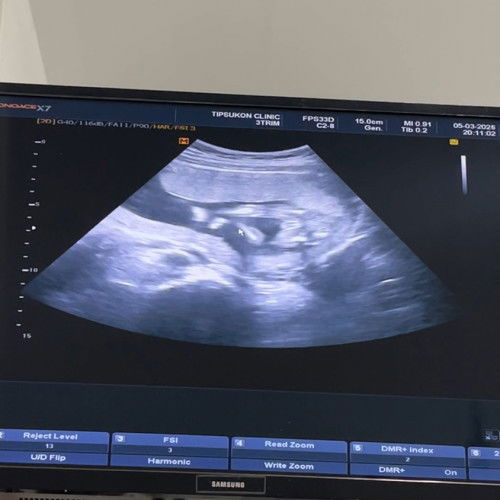

อัลตร้าซาวด์น้อง 9 week

ตอนนี้ท้องได้ 9 สัปดาห์แล้วไปอัลตร้าซาวด์เมื่อวานที่โรงพยาบาลหมอบอกว่ายังไม่เห็นตัวน้องแต่เห็นเป็นก้อนแบบนี้ปกติไหมคะ